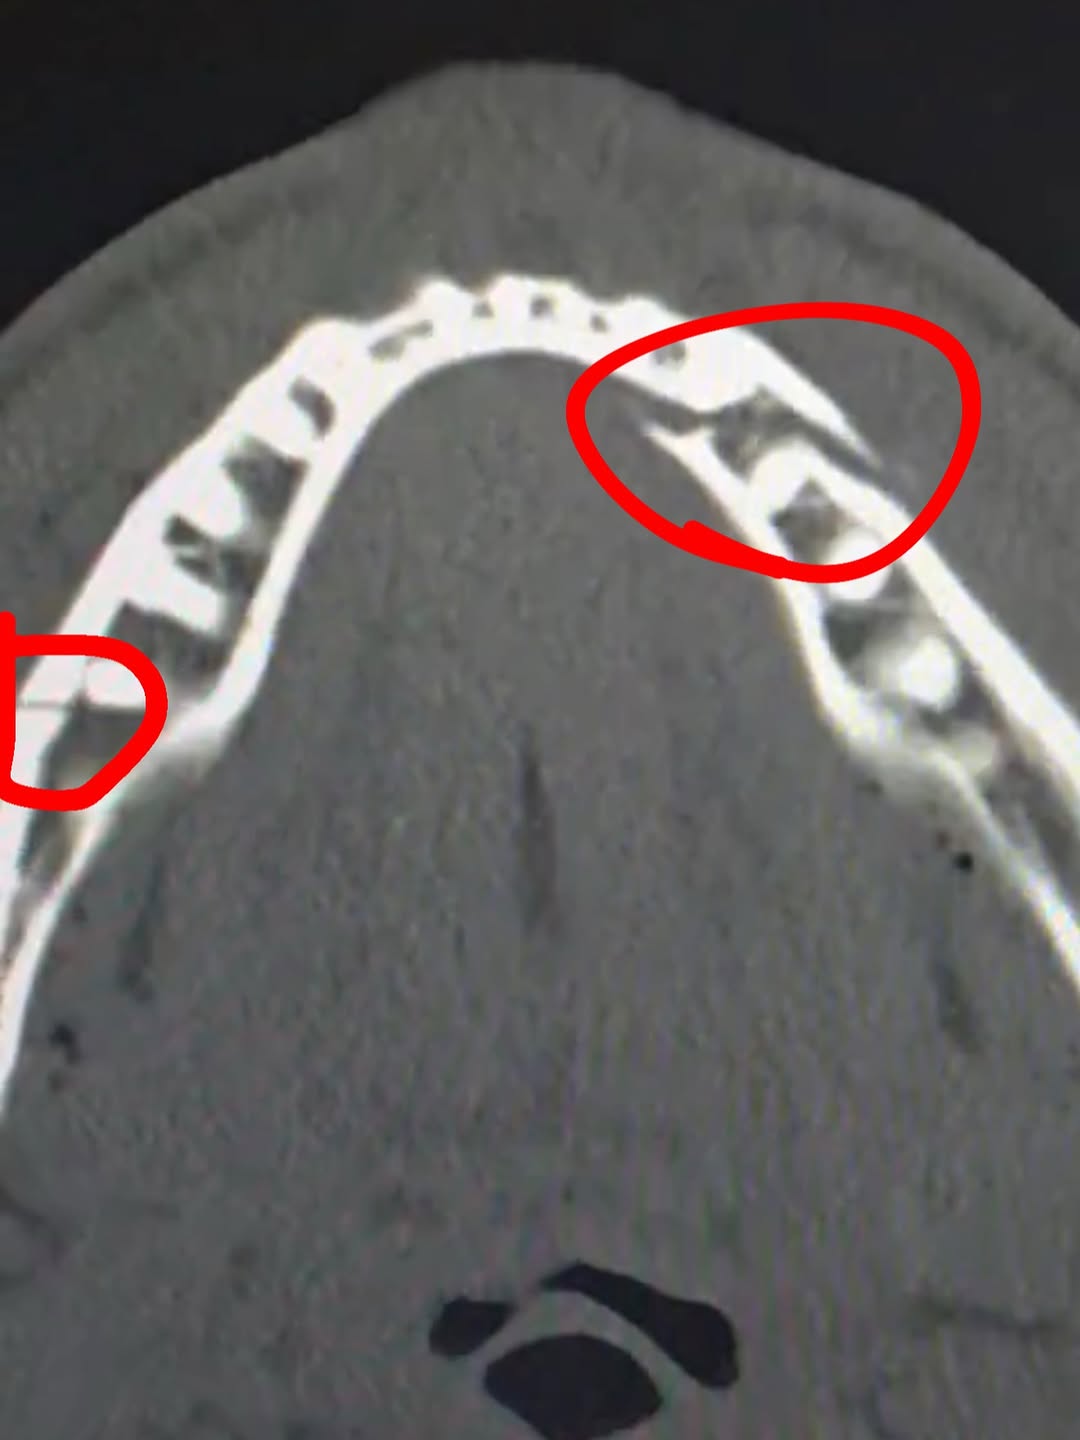

Подозрения быстро подтвердились. Пропустив послематчевую пресс-конференцию, Пол самостоятельно приехал в больницу, где ему сделали рентген. Позже он опубликовал снимок в соцсетях с подписью:

«Двойной перелом челюсти.Дайте мне Канело через десять дней».